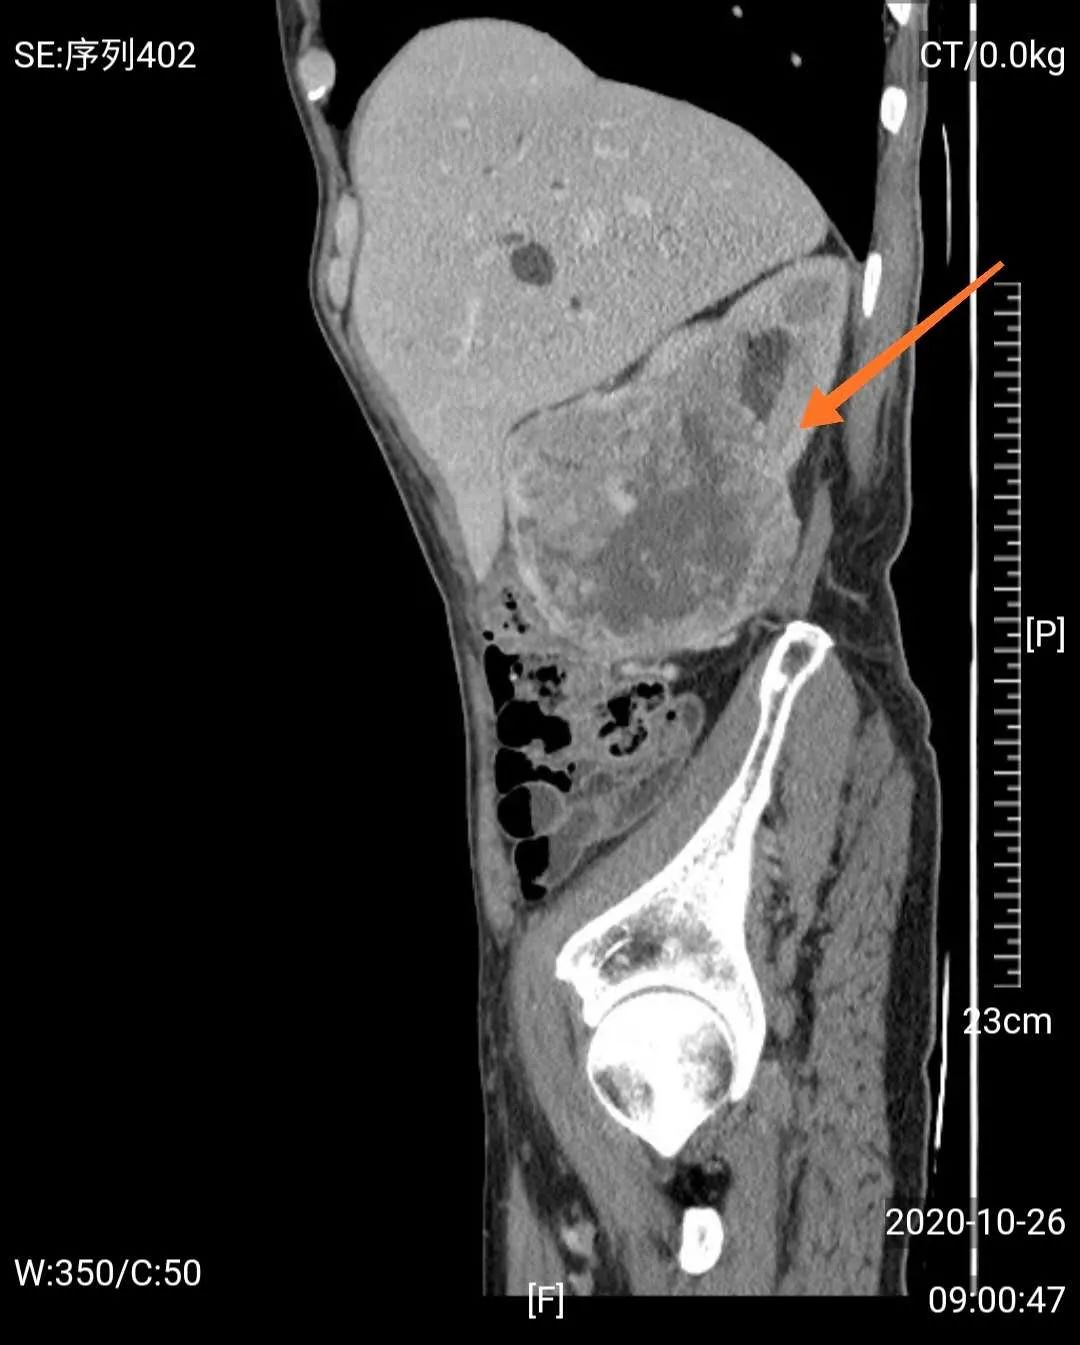

然而,门诊泌尿系超声检查发现,梁爷爷除了前列腺增生外,还有一个可怕的问题——右肾巨大肿瘤,考虑右肾癌可能性大。

经MDT团队研究,影像学团队分析认为老人诊断右肾癌相对明确,手术治疗是首选方案;心血管及肺病科团队认为老人虽然年龄大,高血压病史,但血压控制较好,心肺功能评估认为手术风险属于轻度;肿瘤科认为患者手术指征很明确,目前一般情况好,预期寿命长,内科治疗效果不及外科手术;中医治疗可以在外科手术后辅助,不能仅靠中医治疗。泌尿外科团队认为患者诊断考虑右肾癌,且左肾功能正常,右肾肿瘤巨大,建议根治性手术切除,考虑老人年纪大,开放手术创伤大,出血多,建议采用3D腹腔镜微创治疗。

如前所说的血尿,是肾癌的常见症状,而当肾癌患者发现有肉眼血尿时,表示肿瘤已经侵入肾盏、肾盂了。随着肿瘤生长,会牵拉肾包膜,或者侵犯到邻近的腰肌和器官,此时会产生腰部的疼痛,一般呈钝痛或隐痛;肾内的血块通过输尿管还会引起肾绞痛。假如是比较大的肿瘤,还可以在患者腰部或腹部触摸到肿块。血尿、疼痛、肿块称为肾癌的“三联征”,但多数患者只会出现其中之一或两项,而这时肾癌都已经发展到较晚期了。